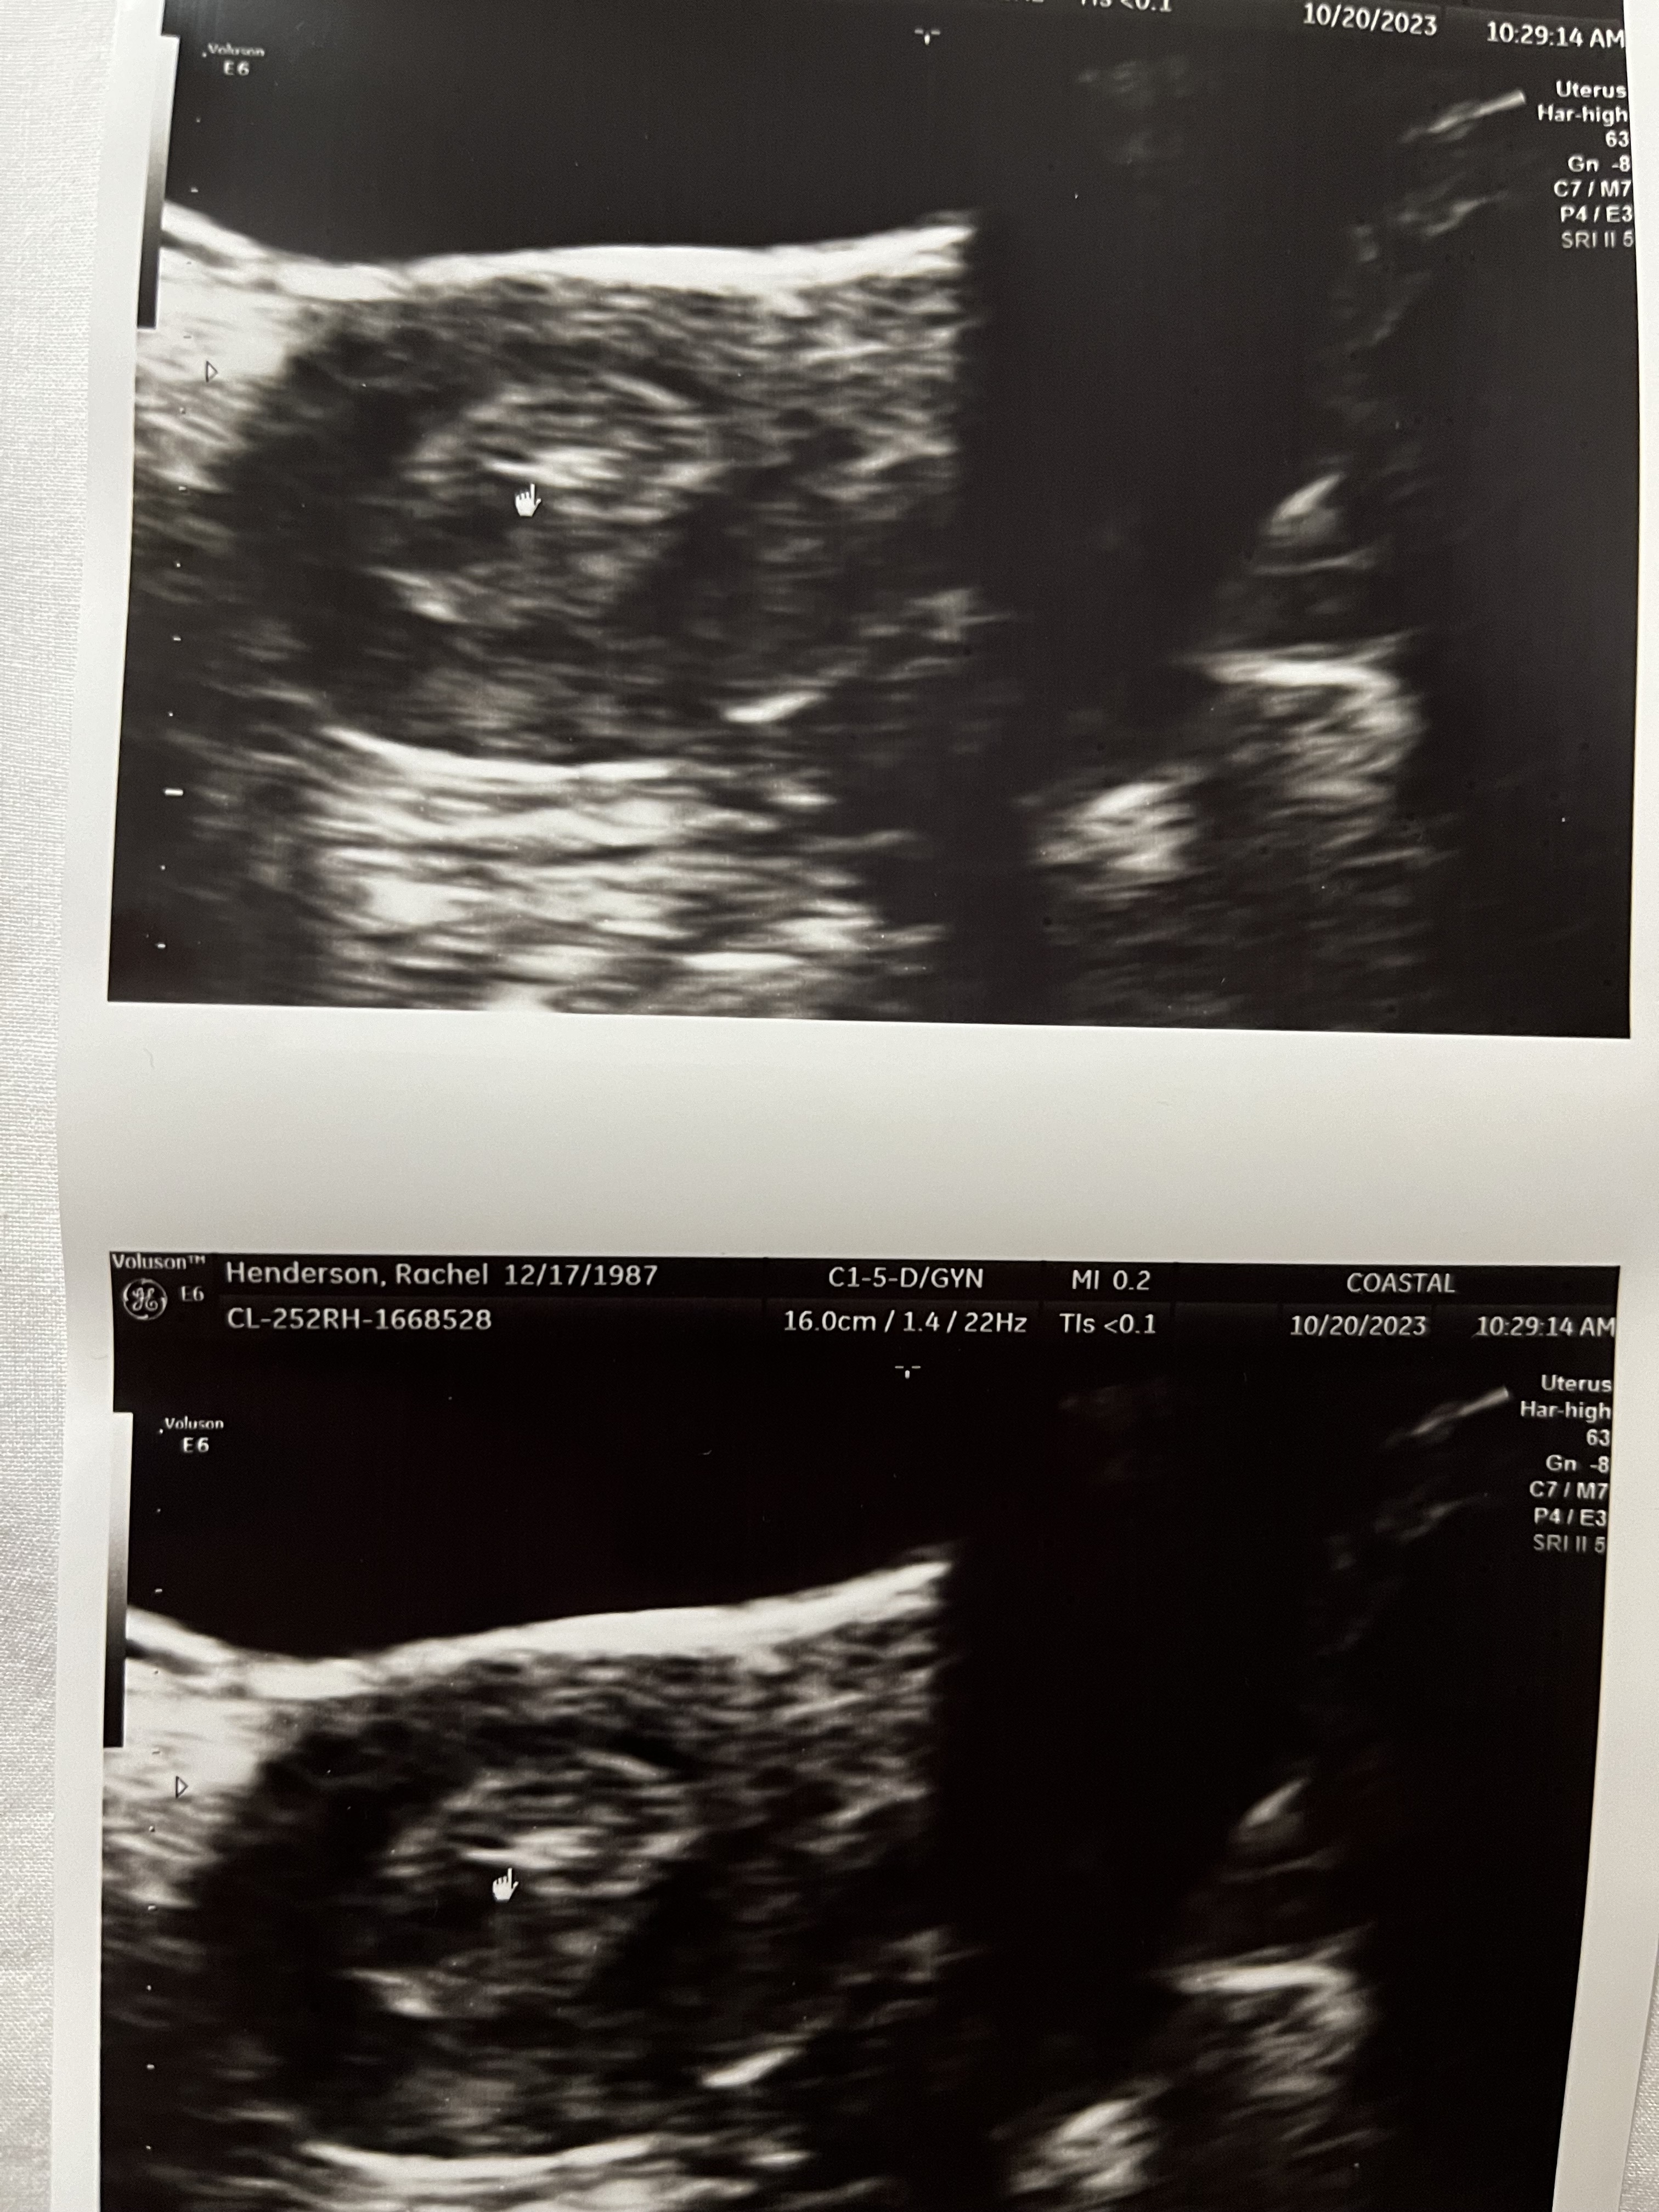

The second image is our embryo! It is graded 5AA. 5 is for the diameter (I think in mm) and A for the baby side (left half I think) and A for the placental side.